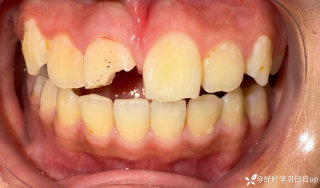

病例信息【患者信息】:男、16岁【主诉】:全身皮肤瘙痒伴皮疹10分钟【现病史及既往史】:10分钟前患者骑摩托车行驶途中,突感全身瘙痒,奇痒无比伴全身发热,心跳加快。急诊就诊,既往无类似病史,否认咽喉梗阻感、胸闷、气短、呼吸困难、恶心、呕吐、腹泻、乏力等不适。【检查】:血压:138/80mmHg,心率:116次/分,呼吸:21次/分。【临床诊断】:急性荨麻疹【治疗经过及结果】:给予吸氧、肌注扑尔敏1支,口服氯雷他定1片,静滴甲泼尼龙40mg后瘙痒明显减退,皮疹消失。病例讨论双手十指及双足未纹身,护士最后穿刺左手大拇指。